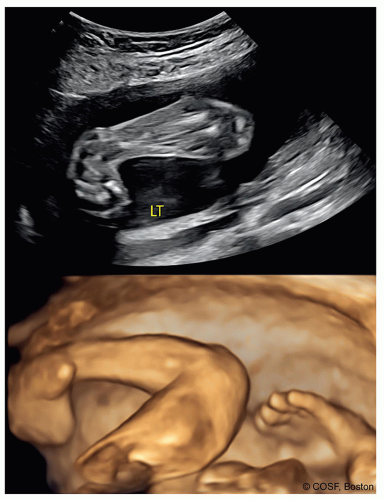

Most clubfeet are diagnosed by ultrasound at 18 to 24 weeks’ gestation in modern times (Figure 27.2). In our state, Massachusetts, well over 90% of clubfeet are diagnosed by ultrasound prenatally. In many cases, families seek information about clubfoot management and potential associated problems

for their unborn child immediately following this fetal diagnosis. Orthopedic surgeons need to provide information to families once the fetal diagnosis of clubfoot is made and construct a plan for management including information about the expected outcome. This will relieve anxiety and provide valuable information to the family. Families may get involved in support groups online or in person, speak with other families with clubfoot diagnosis, and may want to see patients being treated for clubfoot or see cases with long-term follow-up. In the absence of this information, expectant parents may erroneously believe that the diagnosis of clubfoot equates to lifelong disability.